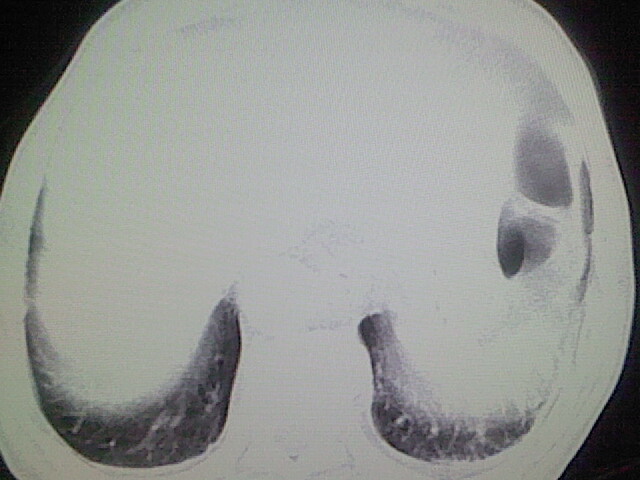

以下是引用zsl6918在2008-8-28 16:49:00的发言:[br]双肺炎性病灶,食管狭窄估计与心房增大压迫所致。

以下是引用xulianj在2008-8-28 20:36:00的发言:[br]慢支肺气肿伴感染,右上肺陈旧性结核;食道建议胃镜检查。

以下是引用wqs571018在2008-8-28 21:18:00的发言:[br]慢支继发感染,右上肺陈旧性结核;食道建议胃镜检查。